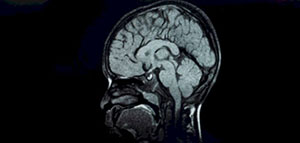

يعدالتصوير بالرنين المغناطيسي للدماغ MRI أحد الطرق الرئيسية لتشخيص ضمور المخيخ تليه الاختبارات خزعة العضل ودراسة الجهاز العصبي المحيطي للطفل المصاب كما قد يوصي الطبيب بفحوصات أخرى تتضمن ما يأتي